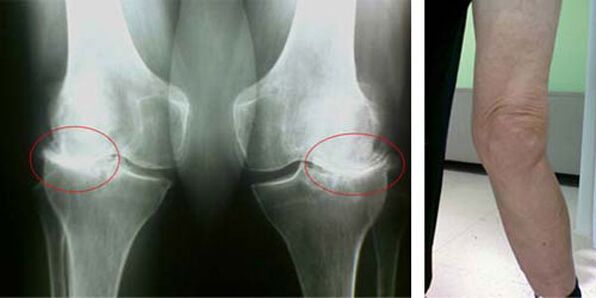

Τα αρχικά στάδια της εμφάνισης μιας τέτοιας παθολογίας όπως η αρθροπάθεια της άρθρωσης του γόνατος δεν εκδηλώνονται με κανέναν τρόπο οπτικά. Ωστόσο, μετά από ένα χρονικό διάστημα, ο ασθενής αρχίζει να παρατηρεί σημάδια παραμόρφωσης στο γόνατο, καθώς και μια χαρακτηριστική καμπυλότητα κατά μήκος του άξονα του κάτω ποδιού (κατευθυνόμενη προς τα μέσα). Υπάρχει επίσης ένα τραγανό όταν πρέπει να λυγίσετε το πόδι.

Η παρουσία πόνου και περιορισμένης κίνησης στο γόνατο ωθεί ένα άτομο να δει έναν γιατρό και να υποβληθεί σε εξέταση. Για να γίνει αυτό, πρέπει να περάσει εξετάσεις και να κάνει ακτινογραφία της πάσχουσας άρθρωσης. Εάν αυτά τα μέτρα δεν επαρκούν για την ανίχνευση της αρθροπάθειας της άρθρωσης του γόνατος, γίνεται μαγνητική τομογραφία. Με βάση τα δεδομένα που συλλέγονται, ο γιατρός επιλέγει τις καλύτερες μεθόδους θεραπείας.